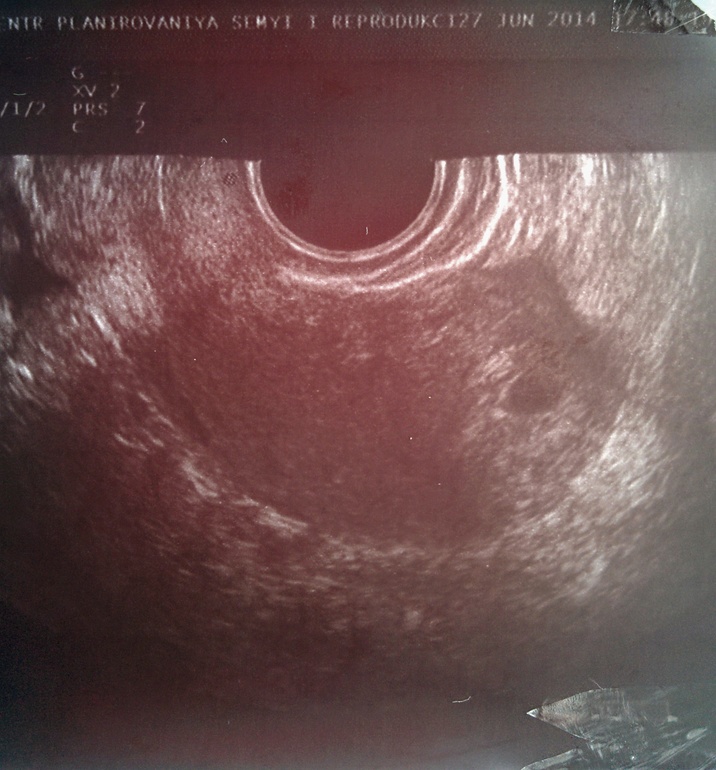

Первое УЗИ и мои новости

Вот уже и первое фото)))))Как это мило!!!!!!Счастливой тебе беременности, моя хорошая!!!!!!!! kisses.gif

Да ну, какое сердечко?! 3 недели от зачатия-ещё даже эмбриончика не видно! Так что можно не торопиться на УЗИ, если только убедиться, что Б  маточная.

super_smilies082.gif с первым УЗИ! У нас такая же фоточка! Лёгкой беременности!

Спасибки! Самая лучшая фотка в моей жизни!